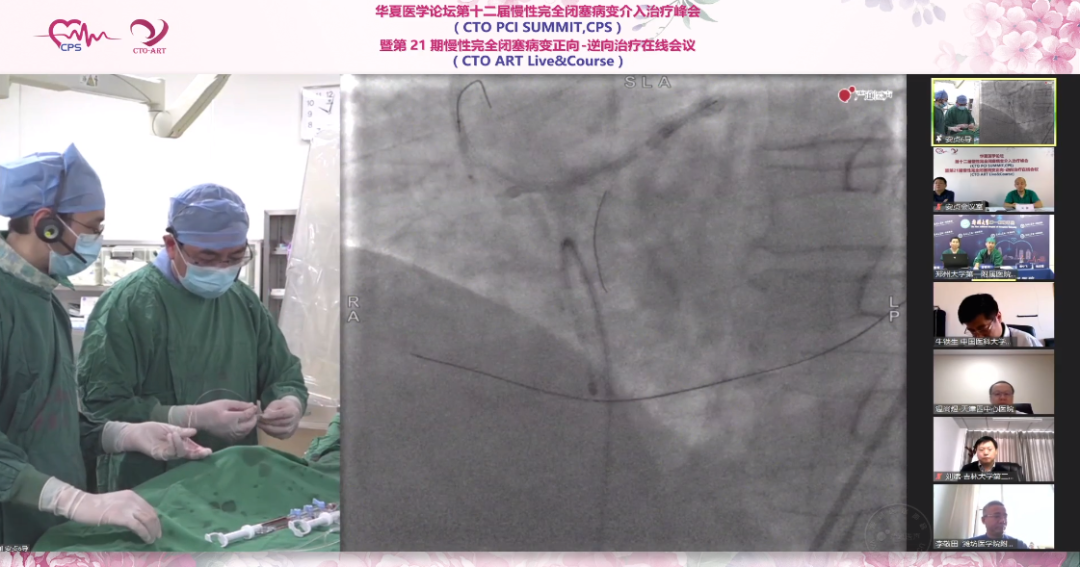

5.更换Pilot200导丝再次尝试但仍无法通过,再更换Miracle12导丝,成功送至后侧支,逆向造影可见远端导丝位于后侧支血管内,导丝成功完全通过闭塞段。

6.使用1.5mm及2.0mm球囊对闭塞病变进行扩张,送微导管更换工作导丝,行IVUS检查。IVUS提示存在支架膨胀不全及贴壁不良,支架内膜增生明显,导丝全程位于真腔内。

7.使用2.5×20mm后扩球囊对闭塞段进行扩张,再次造影示血管再通,再用3.0mm球囊及切割球囊反复扩张观察扩张效果,充分扩张后使用DCB进行治疗。